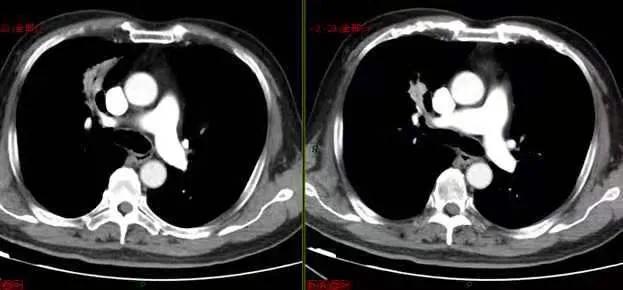

男性 61 岁,因呼吸困难和胸痛就诊,胸片提示左肺内占位;

典型爆米花样改变的肺内错构瘤